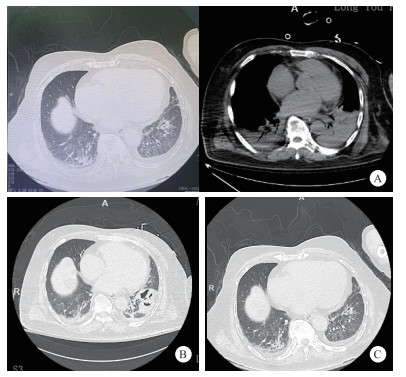

体格检查:体温38.8℃,脉搏101次/min,呼吸35次/min,血压177/57 mmHg(1 mmHg=0.133 kPa),SpO2 90%。神志清,急性病容,呼吸浅快,双肺呼吸音粗,可闻及湿啰音,心律齐,双下肢中度凹陷性水肿。既往高血压病史,不规律服药。否认冠心病、糖尿病等基础疾病。家中饲养宠物犬(5年)。结合患者临床表现特点,诊断考虑脓毒症、急性左心衰,予心电监护,无创呼吸机辅助通气。首次心电图提示频发多源性房早,时呈成对、短阵房速,部分伴室内差异性传导,频发室早,T波改变(图 1-A)。血气分析提示严重失代偿性代谢性酸中毒,血乳酸显著升高(pH 7.022,乳酸13.1 mmol/L)。约15 min后,患者突发意识丧失、口唇发绀,心电监护提示室颤,予胸外按压、电除颤,同时气管插管、机械通气。后患者转复窦律,复查心电图如图 1-B所示。抢救过程中患者再次室颤,予紧急电除颤后转复窦律,经充分镇静、镇痛,呼吸机支持,病情逐渐趋于稳定。完善床旁心脏超声:提示左室增大,左心收缩功能显著下降,射血分数30%。实验室检查提示:肌钙蛋白I 0.345 μg/L(参考值< 0.01 μg/L),血白细胞计数10.8×109/L,中性粒比例94.0%,C反应蛋白32.50 mg/L,肌酸激酶438 U/L,肌酸激酶同工酶3.83 U/L,D-二聚体1.27 mg/L,前降钙素原94.42 ng/mL,NT-proBNP 2 917.70 pg/mL。甲/乙流、新冠相关检测结果均阴性。胸部CT(图 2A)提示两下肺渗出,部分实变。

| 注:A为入院当日(2024-02-18)双肺下叶斑片状渗出影(白色箭头);B为治疗第8天(2024-02-26)左下肺空洞形成(黑色箭头);C为治疗第31天(2024-03-19)病灶吸收伴纤维条索影(黑色箭头) 图 2 胸部CT动态演变 |

患者病情稍稳定后拟脓毒症、脓毒性心肌病、心室颤动转ICU进一步治疗。初予经验性头孢哌酮钠舒巴坦(2:1,3.0 g q12 h ivgtt)抗感染, 去甲肾上腺素联合肾上腺素抗休克,维持内环境稳定,间断气管镜下吸痰等处理。次日出现少尿,血肌酐升高,予连续性肾脏替代治疗(continuous renal replacement therapy, CRRT)。后肺泡灌洗液及血液宏基因组二代测序(metagenomic next-generation sequencing, mNGS)提示多杀巴斯德杆菌阳性,序列数11425,痰培养及血培养均提示血孪生球菌感染,痰真菌培养阴性,结核Xpert-MTB检测阴性,多次痰找抗酸杆菌检测阴性。根据病原学检测结果,调整抗感染方案为:头孢哌酮钠舒巴坦钠(3.0 g q12 h ivgtt)联合莫西沙星(0.4 g/d ivgtt)。2024-02-26日复查胸部CT提示左肺下叶空洞形成(图 2-B)。经积极治疗,患者感染逐渐控制,总体病情趋于稳定。2024-02-29呼吸机脱机、拔管,后转呼吸科病房,03-19复查胸部CT,提示双肺炎性渗出较前吸收,左下肺空洞较前减小(图 2C)。经多学科团队协作治疗后,患者出院时心功能分级(NYHA)Ⅱ级,6 min步行试验距离达380 m。出院诊断:脓毒症、脓毒性休克、脓毒症心肌病、脓毒症凝血功能障碍、多杀巴斯德菌感染、重症肺炎、重度成人急性呼吸窘迫综合征、心源性猝死、心室颤动、急性肾衰竭、糖尿病。3个月后随访LVEF恢复至55%,未遗留明显后遗症。